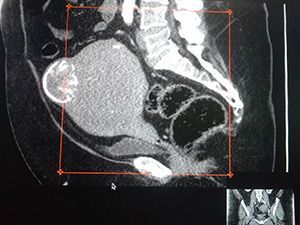

Компьютерная томография (КТ) органов малого таза

КТ малого таза является современным неинвазивным методом рентгенологической диагностики, позволяющим выявить патологии, повреждения и новообразования лимфатических узлов, мочевого пузыря, сосудов исследуемой области. Помимо этого, КТ органов малого таза позволяет выявить патологии предстательной железы у мужчин, матки и придатков — у женщин. КТ малого таза с контрастом назначается в тех случаях, когда необходимо ещё лучше визуализировать мягкие ткани и сосуды.